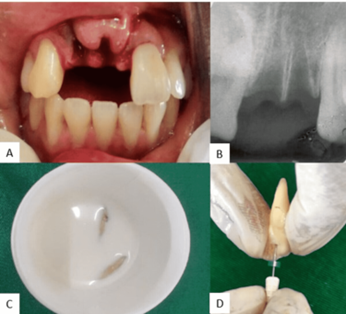

- Răng bật ra khỏi xương ổ (avulsion): Răng rơi hoàn toàn khỏi miệng, cần cấp cứu nha khoa khẩn cấp.